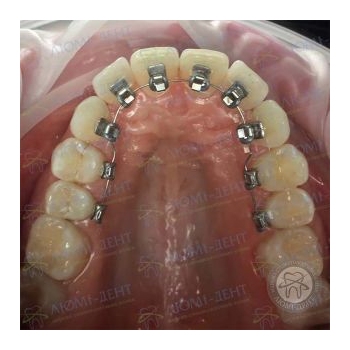

Фото. Работа врача ортодонта с пациентом клиники «Люми-Дент».